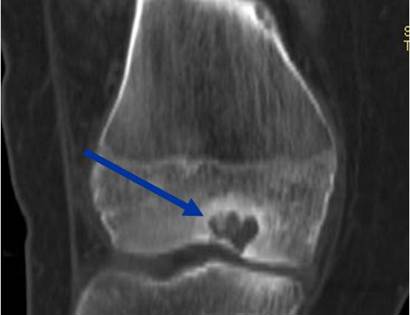

• • The work-up for ABCs often consist of a physical examination, scans including X-Ray, MRI and Bone Scans. A CT scan is sometimes used.

• • The diagnosis is often confirmed with a biopsy, which means taking a sample of tumor and having it analyzed under a microscope. Under a microscope, chondroblastomas look like immature “baby” cartilage cells. Calcifications may be seen that weave through the tumor, resembling a “chicken wire”. Also a “cobblestone” appearance is described by pathologists. In many instances the biopsy can be performed at the same time as the definitive surgery.

Radiographic imaging is used to help form a diagnosis of Chondroblastoma. Scans include X-Ray, MRI and Bone Scan. CT scan is sometimes used to assess the adjacent bone quality and look for flecks of calcium in the tumor to aid in diagnosis. MRI usually shows extensive swelling around the tumor that is sometimes misinterpreted as a cancer.